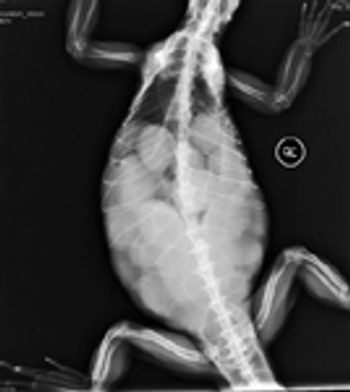

Normal and abnormal radiographs of a variety of conditions in the pet rabbit will be presented.